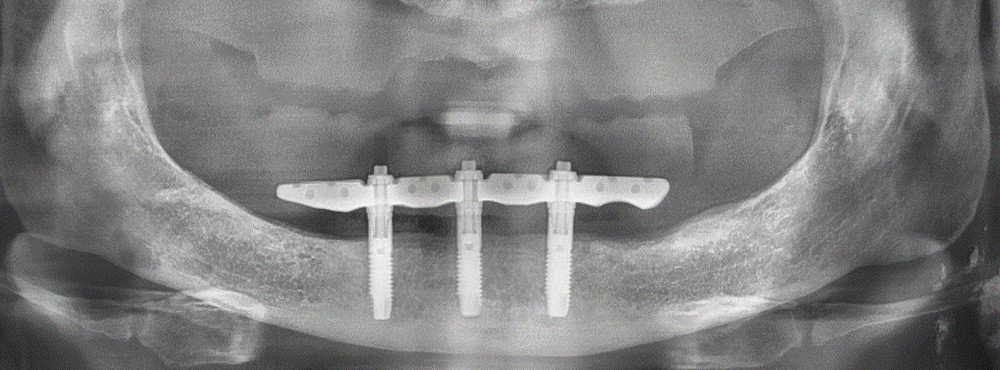

Le patient, édenté total, souhaite une réhabilitation maxillomandibulaire avec une forte demande de fixité pour sa prothèse inférieure. La topographie symphysaire [2], validée par un cliché numérique, nous ouvre l’opportunité d’une mise en charge immédiate d’un bridge sur pilotis type Trefoil, confirmée ultérieurement par le montage directeur (fig. 1) [3].

La planification virtuelle implantaire s’ensuit. Une fois encore, le numérique conforte ses atouts. Les matchings, sous réserve d’une parfaite correspondance, offrent une multitude d’informations optimisant la parfaite concordance entre anatomie osseuse, implants (3 CC RP 5×11,5mm), barre Trefoil et montage directeur (fig. 3). Cette somme d’informations permet alors de visualiser la barre Trefoil au travers du montage directeur.

L’occlusion et les accès prophylactiques sont de nouveau contrôlés. S’ensuivent les séquences de maintenance classiques. Un contrôle radiographique (fig. 8) ainsi qu’une surveillance annuelle sont mis en place.